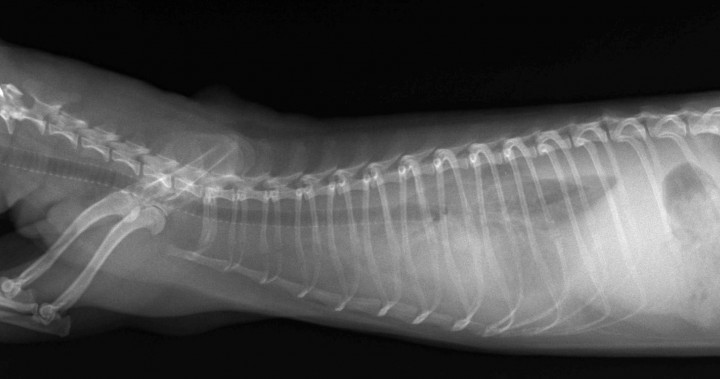

Hurón macho de cuatro meses de edad, no castrado, que presentaba hiporexia, letargo, heces blandas, taquipnea (58 resp./min) y respiraciones superficiales. El animal había convivido unas semanas antes con un visón (Mustela lutreola), aparentemente sano. Las radiografías mostraban derrame pleural (Fig. 1). En el proteinograma de este animal (Tabla 3) destacaba una marcada hipoalbuminemia y una hipergammaglobulinemia policlonal muy evidente.

<p>Radiografía de tórax (vista lateral). Efusión pleural en un hurón diagnosticado de enfermedad aleutiana.</p>

Radiografía de tórax (vista lateral). Efusión pleural en un hurón diagnosticado de enfermedad aleutiana.